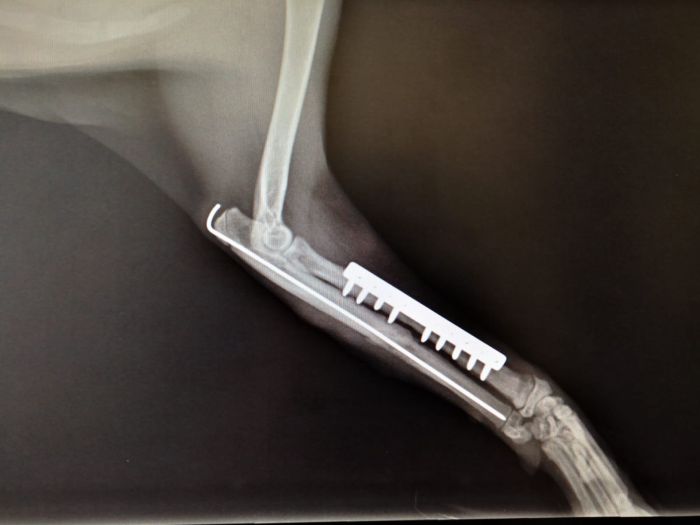

Plattenosteosynthese

Hierbei wird eine Metallplatte  als "Kraft (über-) träger zwischen den Knochenbruchstellen verwendet. Es gibt es eine Vielzahl an Platten ( Abstützplatte, Neutralisationsplatte, Kompressionsplatte, etc.) mit diversen Größen und Längen. Die Metallplatte wird mit speziellen Schrauben (z.B.: Corticalisschrauben / Spongiosaschrauben / ...) am Knochen fixiert.

Fall 1

Fall 2

Fall 3